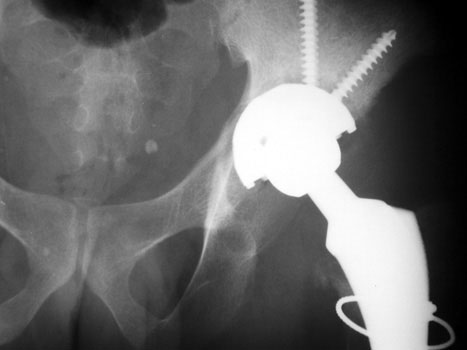

INFECTION

Resection of hardware, cement spacer placement

Cement spacers are antibiotic impregnated, allowing for local dispersal of antibiotics.

• Maintain leg length

• Minimize dead space

• Preserve soft tissue planes

• Facilitate ease of revision arthroplasty

Cement spacers are fabricated in the surgical suite using methylmethacralate cement impregnated with antibiotics sensitive to cultured organisms. A Rush rod is cut and bent to 120 degrees to mimic the femoral neck-shaft angle. Antibiotic impregnated cement is placed into a blue bulb syringe which simulates the femoral head contour and allowed to dry. The plastic is then removed. A second batch of cement is prepared and formed around the femoral shaft portion of the Rush rod.